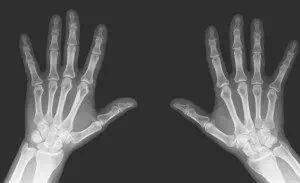

60 на сто от хората стигат от трайна нетрудопсопобност вследствие на мускулно-ставни заболявания. Д-р Наталия Маринова – ревматолог в частна болница посочи: „Най-големите разходи се дължат на загубата на работопособност. Поне 50 процента от пациентите се инвалидизират в първите 10 години и затова ние трябва да бъдем нащрек и още в първите години да отрежем главата, както се казва, на това заболяване“.